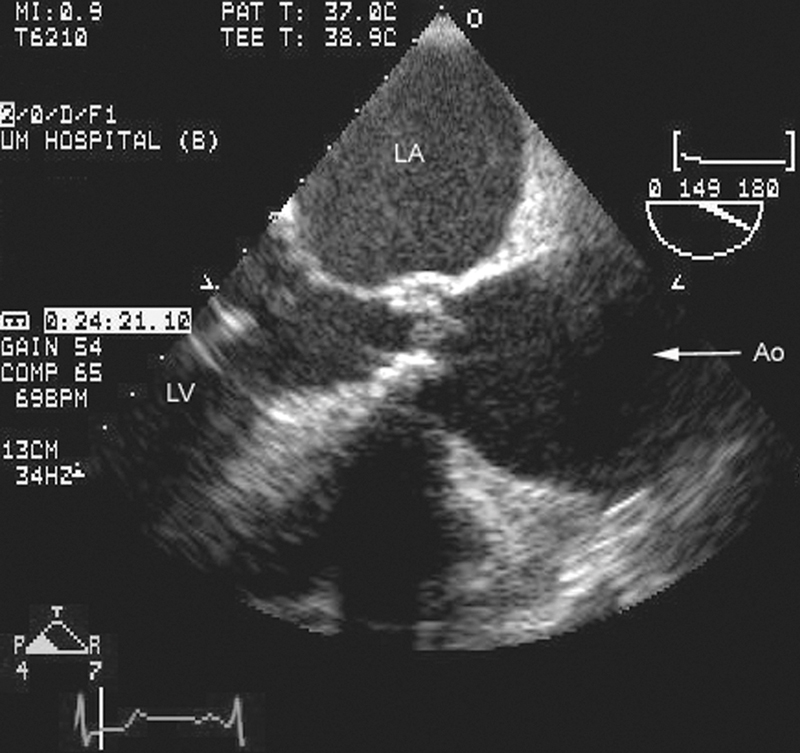

فحوصات تشخيصية لبعض امراض القلب والشرايين التاجية